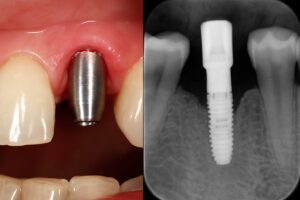

What Are Dental Implants?

A dental implant is a titanium post placed in the jaw to act like a tooth root. An abutment connects the implant to a crown, bridge, or denture. Unlike bridges, implants don’t rely on neighboring teeth. Unlike removable dentures, they’re fixed and help preserve bone.